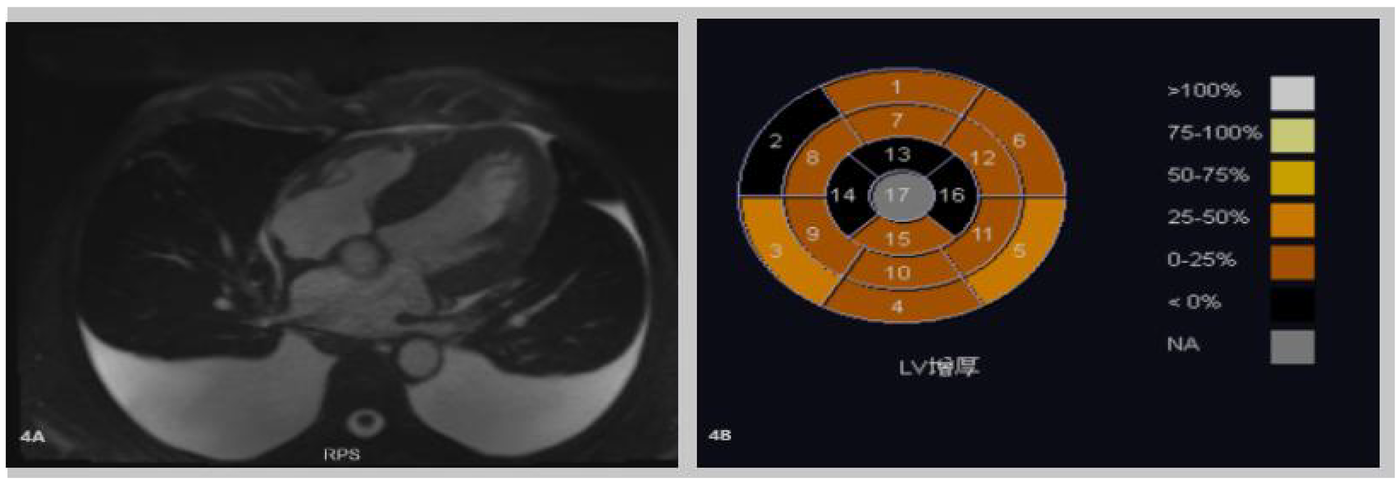

Cardiac enhanced MRI (Figure 4) demonstrated thickening of the left ventricular myocardium with abnormal perfusion and enhancement changes in the right ventricular myocardium, indicative of myocardial amyloidosis. A small amount of pericardial effusion was also noted, along with slight regurgitation of the mitral and tricuspid valves during systole.

Figure 4

(A,B) Cardiac-enhanced MRI illustrates thickening of the left ventricular myocardium. Abnormal perfusion and enhancement changes in the right ventricular myocardium indicate myocardial amyloidosis. A small amount of pericardial effusion is also noted.